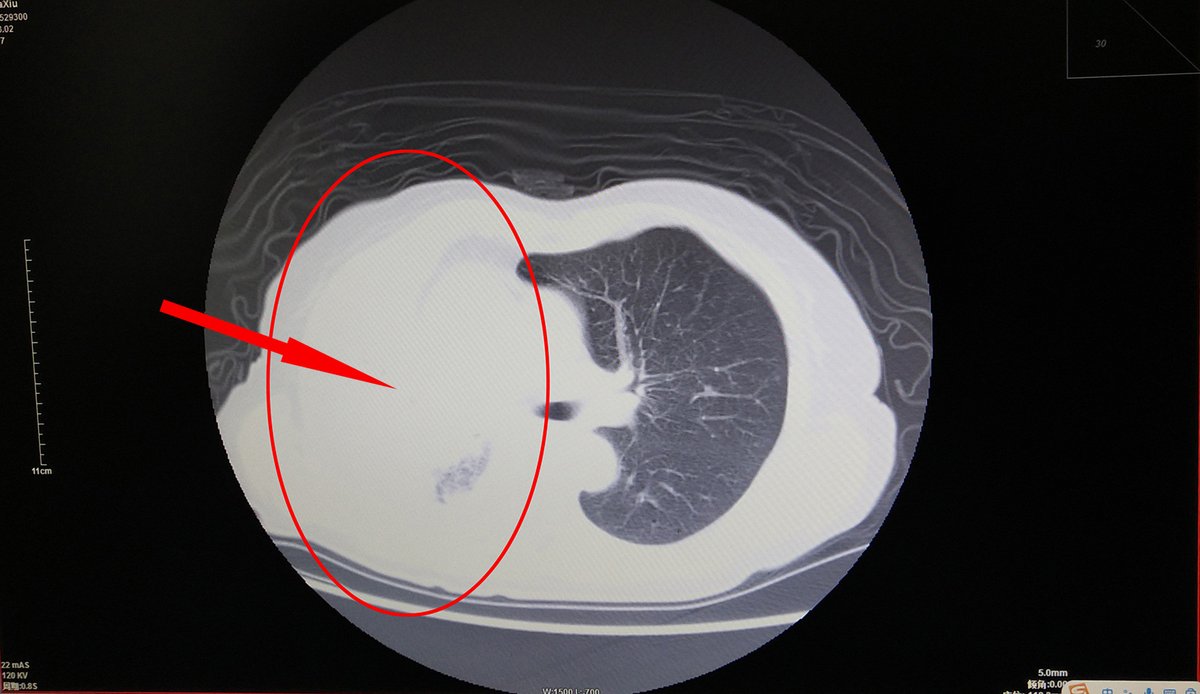

70多岁的王奶奶因间断咯血,在当地卫生院治疗两天无明显好转,吃不香、睡不好,精神状态每况愈下。于2月27日到荆门二医求治,门诊胸部CT显示右肺感染严重、支气管黏液形成(整个右肺呈白色)。正值“新冠肺炎”疫情,王奶奶经核酸检测筛查为阴性后,次日转入呼吸内科保守治疗稍有好转,咯血原因待查。

影像显示整个右肺呈白色